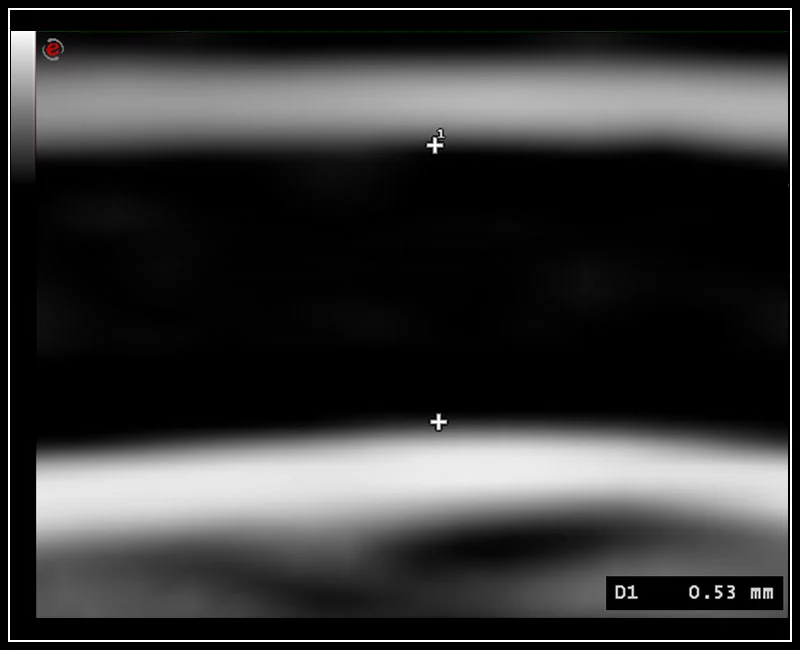

MyLab™X1 Go - Cardiovascular IMT

MyLab™X1 Go - Cardiovascular IMT